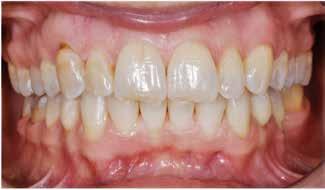

Fig. 5. A, B. Smil og kæbeforhold før og efter. Et bredere smil med korrektion af de laterale mørke rum. C-F. Harmonisk hældning af overkæbe- og underkæbeincisiver, rekonstruktion af den tabte tandsubstans efter nivellering af gingivaniveau og optimal bukko-lingval placering til direkte plastbehandling.

5. A, B. Smile and jaw relationships before and after. A wider smile with correction of the lateral dark spaces. C-F. Harmonious inclination of the upper and lower jaw incisors, reconstruction of the lost tooth substance after leveling the gingival level, and optimal bucco-lingual positioning for direct plastic treatment.